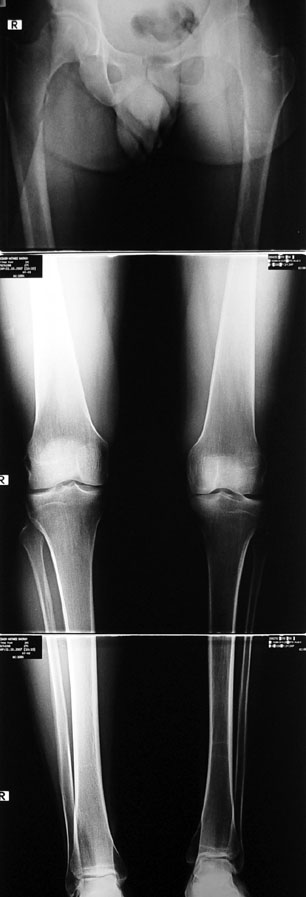

Many patients don’t want to use a shoe support thicker than 2 cm. For length differences between 2 cm and 5 cm, shortening may be considered for tall patients. This can be performed in growing children with a small, minimally invasive, uncomplicated procedure called epiphysiodesis. This means surgical disruption of one or more growth plates. There is a growth plate at the ends of femur, tibia and fibula; this procedure does not halt all growing of the leg. The growing of the longer leg is calculated and halted to allow the shorter leg to catch up.If the procedure is performed at a too early or too late age, the correction may be too much or too little, respectively. Hence, it is important to accurately calculate the most appropriate age for epiphysiodesis. When and at which bone segment epiphysiodesis will be performed shall be calculated by the doctor using different methods such as Gren-Anderson diagram, Moseley curve or Paley’s multiplier method.Epiphysiodesis is not an option for adults because growth plates ar closed. In adults, a bone segment has to be excised surgically in order to shorten the leg. This is usually performed at femur and bone is later fixed with an intramedullary nail. The biggest advantage of this system is that it acutely provides limb length equality for discrepancies less than 5 cm. The common disadvantage of epiphysiodesis and shortening is the shortening of total height of the patient. Because we don’t advice shortening more than 5 cm, height loss can’t be more than 5 cm. For patients who don’t want an epiphysiodesis or shortening operation for length inequalities less than 5 cm, limb lengthening can be preferred in order to equalize the length difference.This can be combined with epiphysiodesis and shortening to decrease a need for another lengthening operation or to decrease the lengthening amount required.

This includs lower limb shortness which occurs following growth plate disruption and growth arrest, Ollier’s Disease, multiple osteochondomatosis, poliomyelitis, infection, radiation (radiotherapy), cerebral palsy, spina bifida, club foot and similar disorders. Additional abnormalities are frequent in this group. Many cases can be treated with one or two lengthening operations. If present, deformity can be corrected simultaneously with shortness. For condirtions that damage the hip joint at the first year of life like neonatal sepsis, we reconstruct the hip joint with pelvic support osteotomy in addition to lengthening, and a hip joint with nearly normal function is acquired.